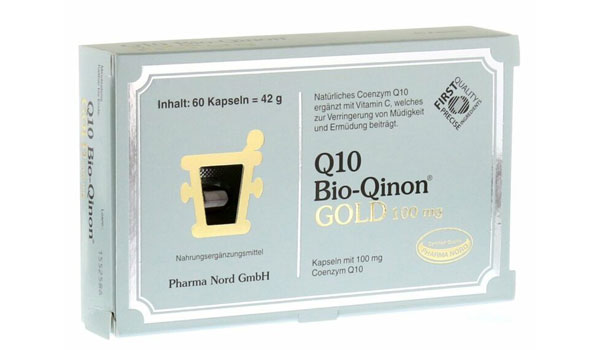

Als ich noch in der Laborforschung tätig war, konnte ich mir selbst helfen: Ich habe mein Wissen über die Regeneration von Stammzellen angewendet, um trotz medizinischer Diagnose zweimal auf natürlichem Weg Mama zu werden. Darüber habe ich ein Buch geschrieben und bereits 2014 als Erste über Pimp my Eggs berichtet – also darüber, wie sich der Körper und die Eizellqualität mit gezielten Lifestyle-Maßnahmen verbessern lassen. Ob Sie meinen Kurs buchen, Experten-Interviews lesen oder einfach Ihre Wissenslücken schließen möchten, hier sind Sie genau richtig. Schön, dass Sie da sind!